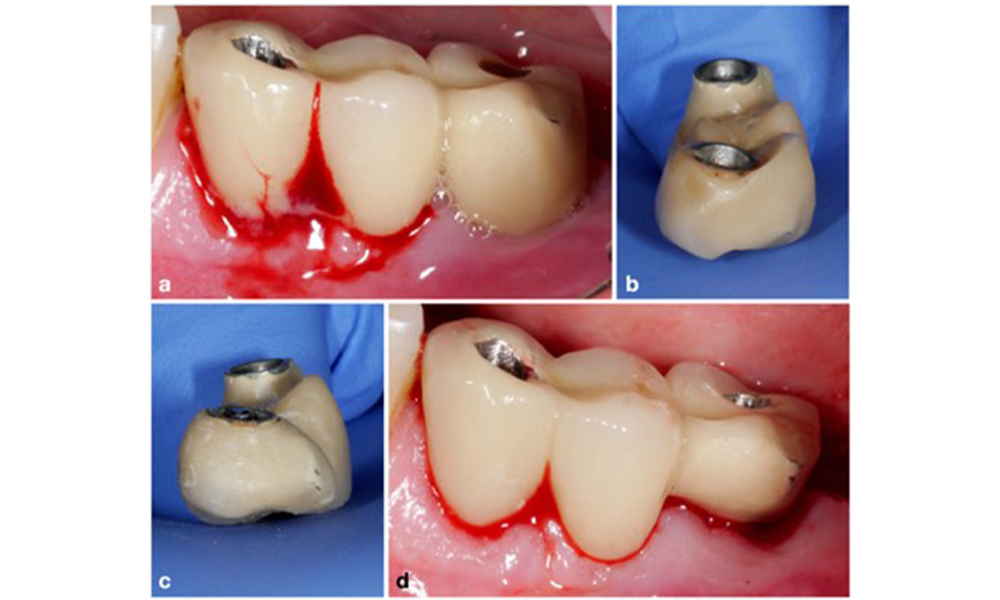

Management of peri-implantitis at implants judged as treatable consists of a non-surgical phase, which is often followed by surgical intervention. For the non-surgical approach, similar measures as those applied for the treatment of peri-implant mucositis are used; based on laboratory experiments air-polishing devices with a subgingival nozzle appear to provide certain advantages in terms of biofilm removal, compared to hand- or ultrasonic instruments (Herrera et al. 2023; Moharrami et al. 2019; Ronay et al. 2017) (figure 9).

Patient case with peri-implantitis. The non-surgical treatment is performed by using the supragingival (a-b) and subgingival handpiece of an air-polishing device (c-d). Removing the supra-construction provides better access to the implant surface (d).

Figure 9. Patient case with peri-implantitis. The non-surgical treatment is performed by using the supragingival (a-b) and subgingival handpiece of an air-polishing device (c-d). Removing the supra-construction provides better access to the implant surface (d).

Yet, the non-surgical approach often has limitations in accessing the implant surface, leading to insufficient decontamination. This is indeed reflected in the clinic, where disease resolution after non-surgical treatment of peri-implantitis is rather unpredictable and recurrence is observed for most cases, i.e., disease resolution was reported to occur only in less than every second case (Ramanauskaite et al. 2021). Therefore, the outcome of non-surgical treatment needs to be evaluated after about 6 weeks, and in cases of moderate or advanced peri-implantitis, surgery should be expected.